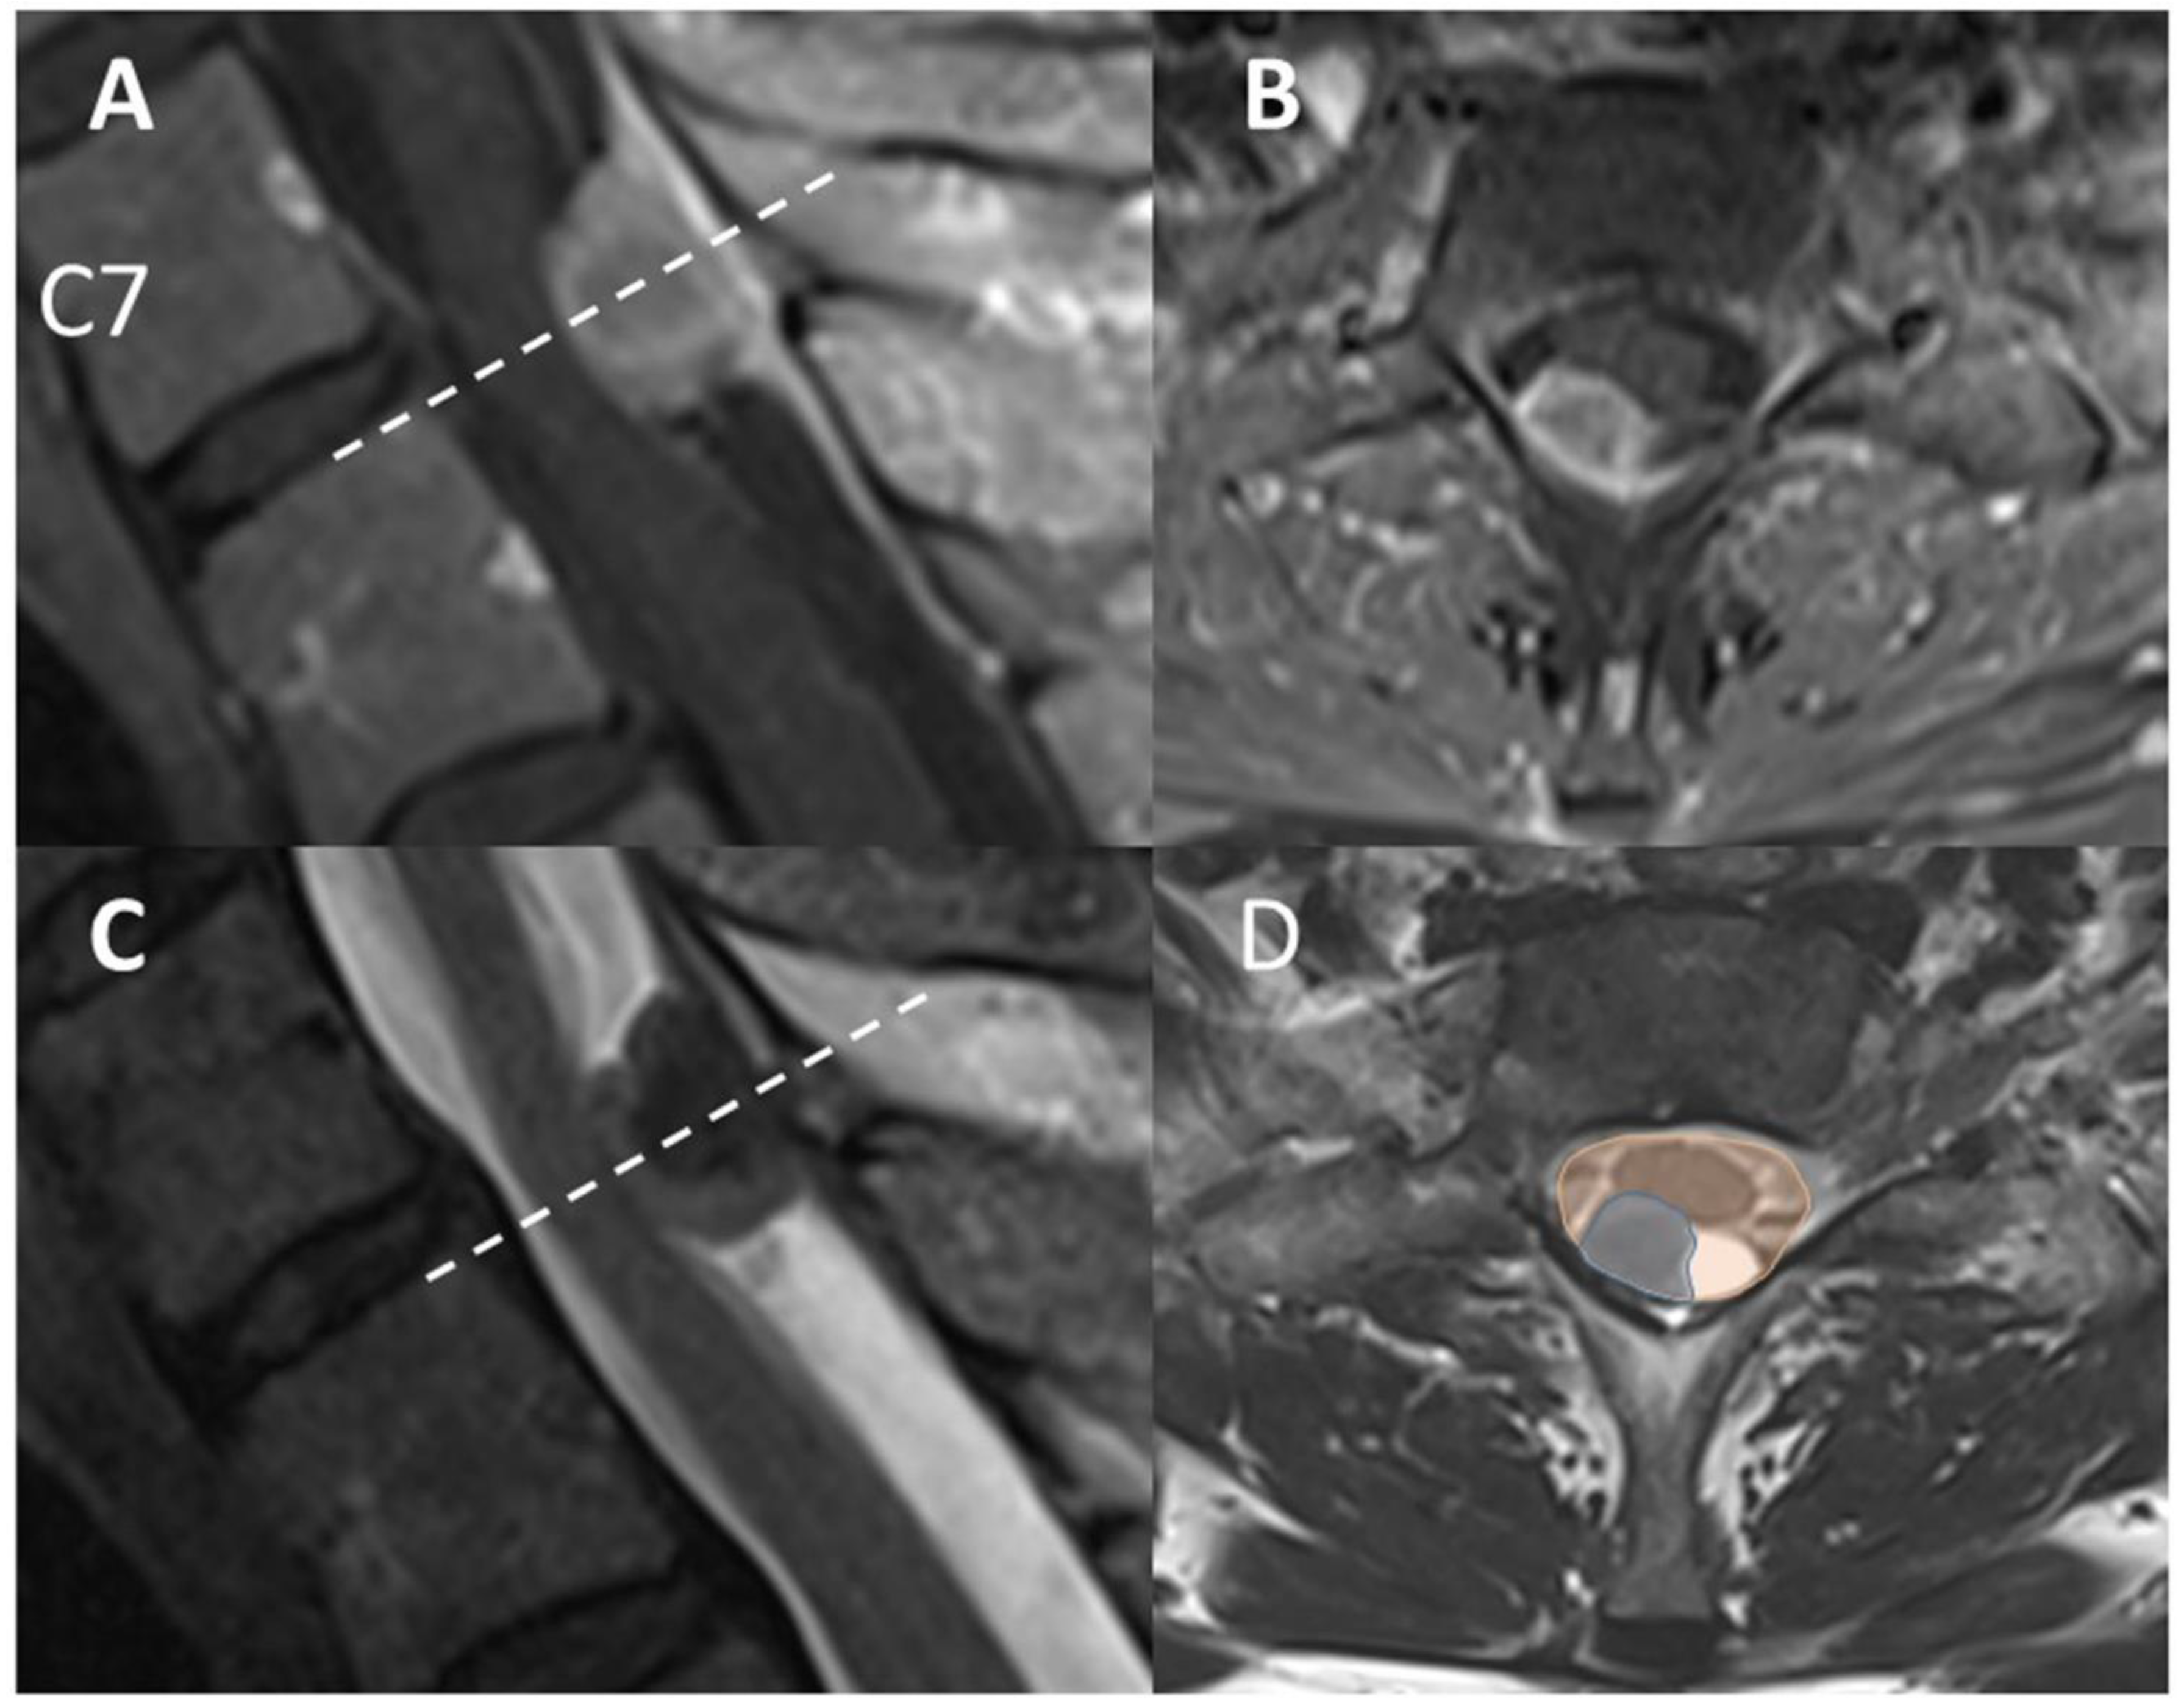

Descriptive Case

- Baro, V.; Moiraghi, A.; Carlucci, V.; Paun, L.; Anglani, M.; Ermani, M.; Saladino, A.; Chioffi, F.; d’Avella, D.; Landi, A.; et al. Spinal Meningiomas: Influence of Cord Compression and Radiological Features on Preoperative Functional Status and Outcome. Cancers 2021, 13, 4183. [Google Scholar] [CrossRef]